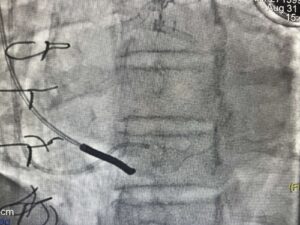

Zabieg wykonywany jest z nakłucia żyły szyjnej i polega na kontrolowanym zwężeniu zatoki wieńcowej przy użyciu rozprężalnego na balonie stentu o kształcie klepsydry. Wskutek zabiegu dochodzi do stopniowego zwężenia pola przepływu przez zatokę wieńcową z redystrybucją przepływu krwi z obszarów o lepszym do obszarów o gorszym ukrwieniu mięśnia sercowego.